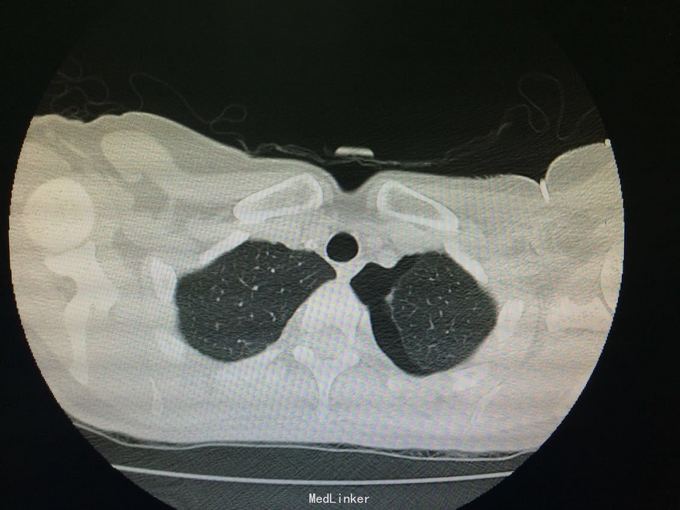

随访:夹管24h后查胸部CT示:左肺下叶炎症、左侧胸腔少量积气、积液。 讨论:该患者是否需要继续闭式引流排气,是否需继续抗生素治疗?